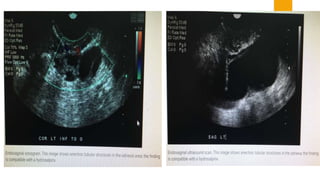

 SONOGRAPHY- Dilated and fluid-filled tubes, fluid in the pouch of

doughlas or adnexal mass are suggestive of PID.

Right Hydrosalpix

Seen In An HSG

 SONOGRAPHY- Dilatedand fluid-filled tubes, fluid in the pouch of doughlas or adnexal mass are suggestive of PID.  CULDOCENTESIS- Aspiration of peritoneal fluid and its white cell count, if exceeds 30,000/mL. is significant in acute PID. Bacterial culture from the fluid is not informative because of vaginal contamination.